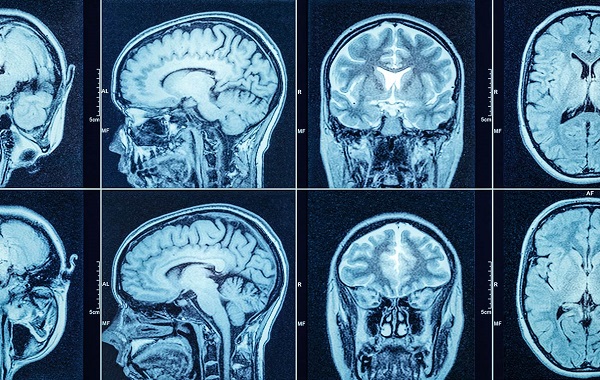

Hình ảnh chụp cắt lớp vi tính sọ não

Chụp cắt lớp vi tính sọ não gọi tắt CT sọ não, CT não, là kỹ thuật chẩn đoán hình ảnh không xâm lấn, sử dụng tia X để tạo ra các lát cắt của não. Thông tin được gửi về máy tính diễn giải và hiển thị dưới dạng hai chiều (2D) hoặc ba chiều (3D) trên màn hình.

Chụp CT não cung cấp thông tin mô não và cấu trúc não chi tiết hơn so với chụp X quang thông thường.